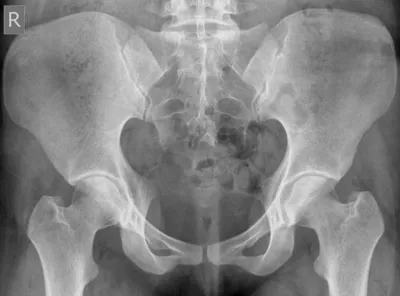

FAI Radiology Images

This collection contains 1 radiology images related to fai, including various imaging modalities such as X-rays, MRIs, CT scans, and ultrasound images commonly used in medical diagnosis and education.